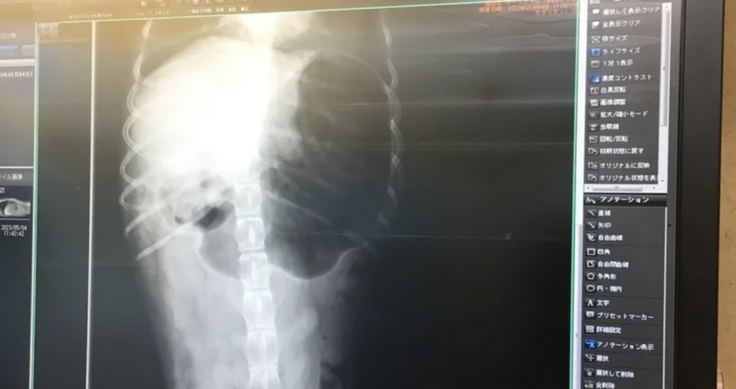

そうすることにより、病院側も着いたら素早く対応することができ、獣医師が予測を立てて診察の準備をすることができます。到着前に獣医師に伝えていたので、到着すると直ぐに診察をしてくださいました。エコー検査とレントゲンを撮り胃捻転と診断されました。

もちろんメリールーの時と同じように動物病院へ電話をして症状を伝え到着時間を伝えていました。先生や看護師さんが外で待っていただいていて、到着と同時にすぐに診察していただき、エコーで胃が膨らんでガスが溜まり捻転しているのを確認して緊急手術となりました。ハナも「あと少し遅かったら間に合わなかった」と言われました。本当に良かった、助かりました。